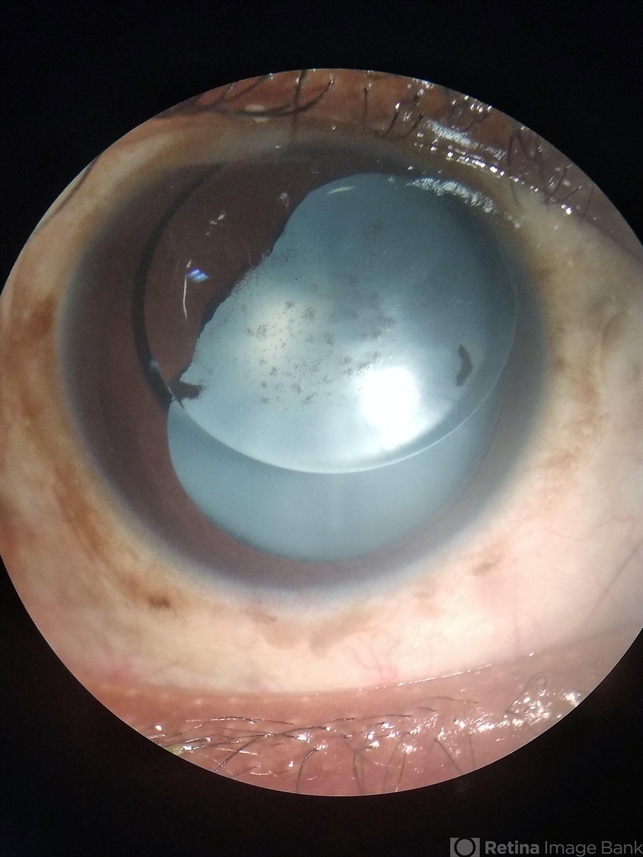

- Post Retinal Detachment surgery

- Dr. Jitendra Kumar, Sri Sankararadeva Nethralaya, Guwahati

- Photo slit lamp biomicroscope

- Anterior chamber photo of a 16-year-old old patient who underwent retinal surgery for traumatic retinal detachment surgery one year prior. Silicone oil is in anterior chamber giving the appearance of a double lens picture. It is looking like a transparent anterior lens and posterior cataract lens.